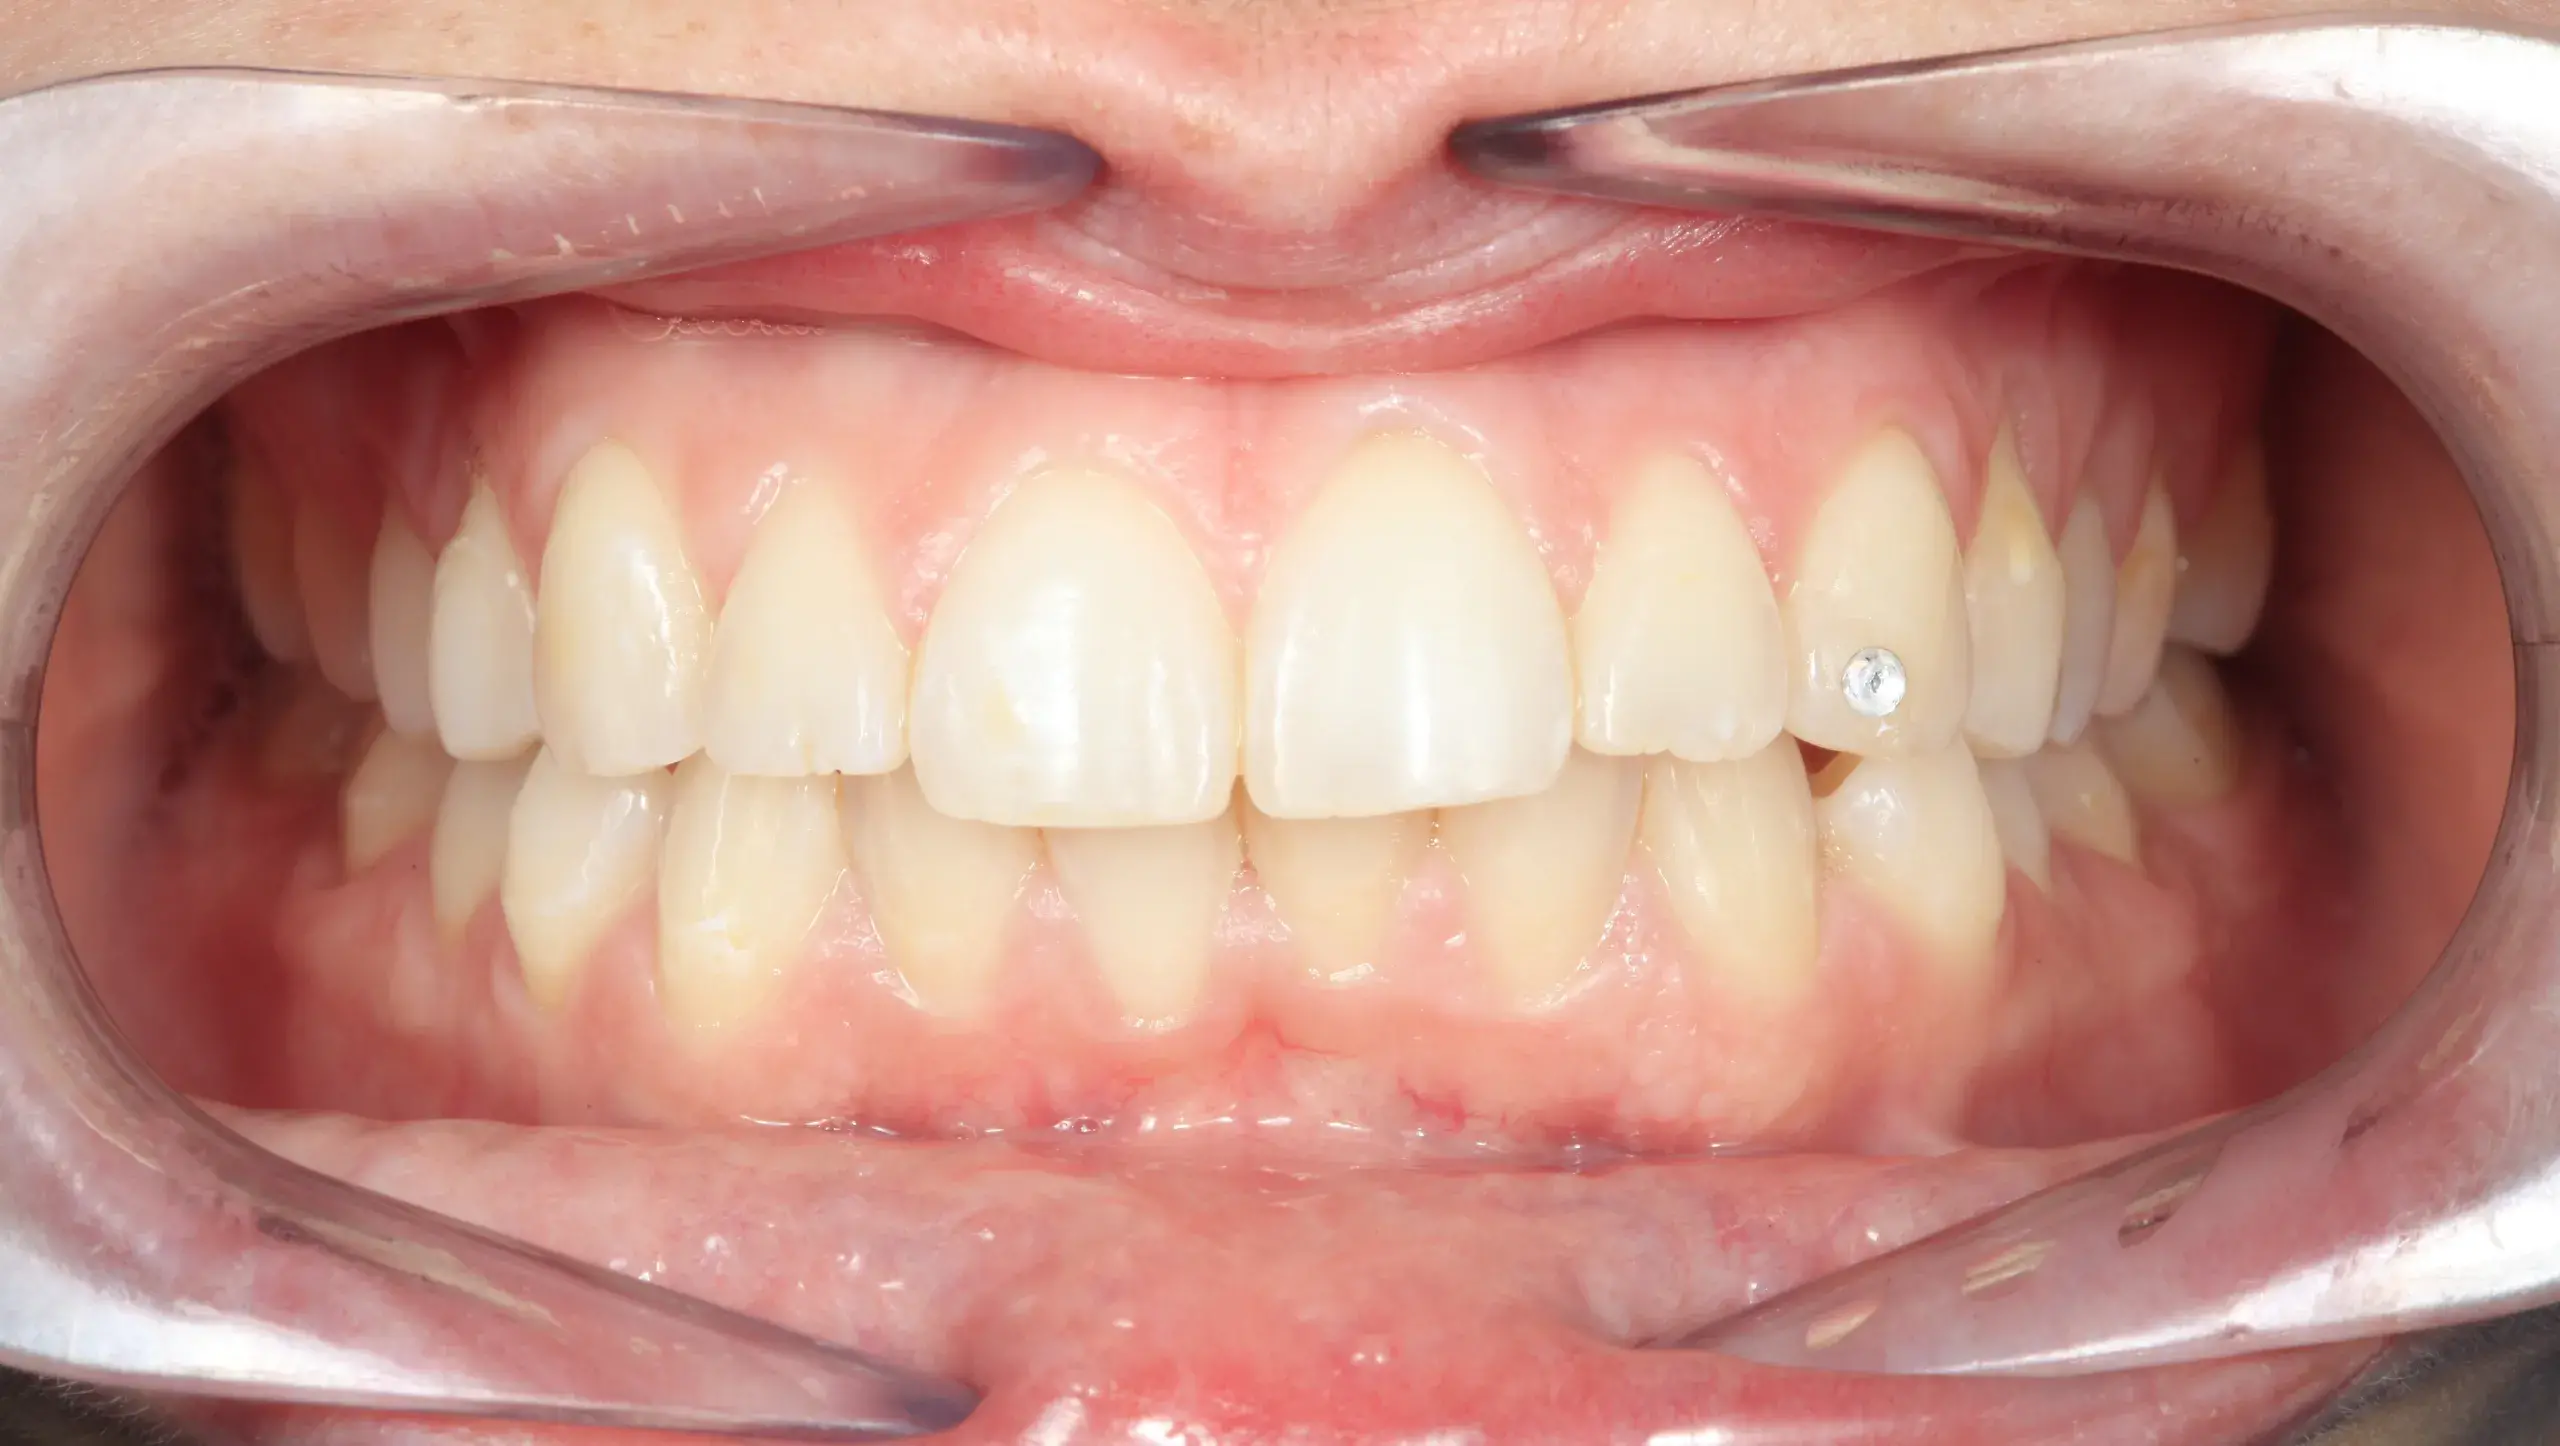

Caso clínico 10: Joyas dentales

Caso clínico 10: Joyas dentales En este caso, se ha realizado un tratamiento de estética dental con la aplicación de una joya dental. Las joyas dentales son una opción no…